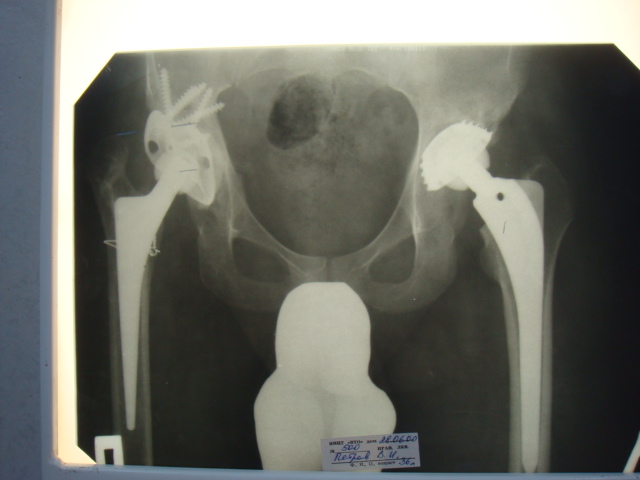

2000 г. установлено кольцо Мюллера и ножка типа Спаторно справа (рис. 1).

2003 г. нестабильность тазового компонента (рис. 2) - протез удален.